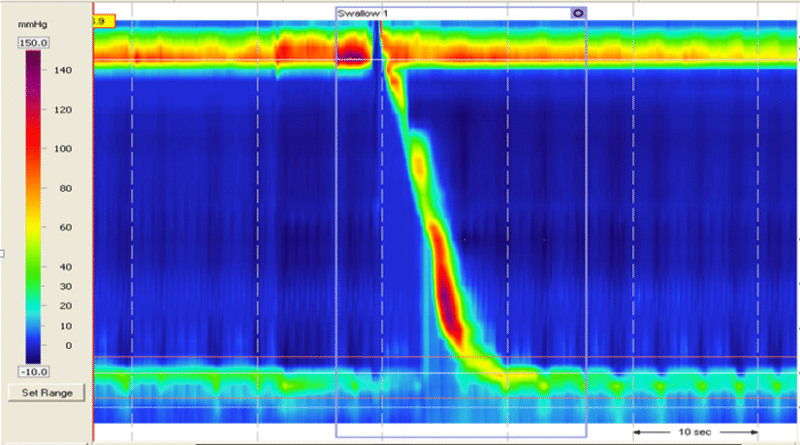

高分辨率食管测压怎么做

食管测压的主要目的是为了明确食管动力学疾病,为医生鉴别诊断及确定进一步治疗方案提供依据。那么检查前我需要注意哪些呢? 1、胃镜检查后间隔一天 2、检查前至少禁食、禁饮8小时,以防呕吐及...